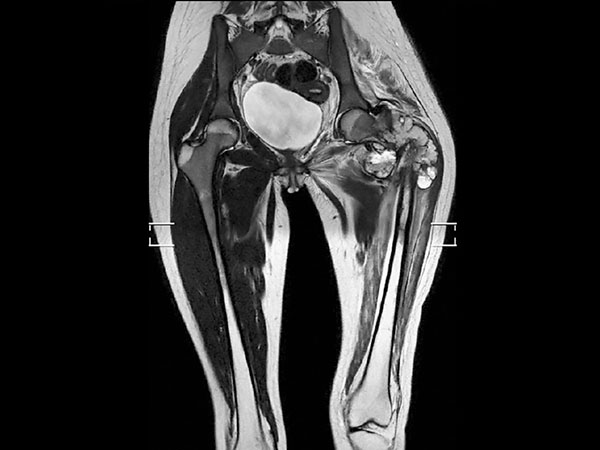

Preoperative MRI in this young girl demonstrates the large tumor with a necrotic component and areas of fluid. The tumor extends down into proximal part of femur. Edema is seen along the femoral shaft down to the knee and in the gluteal muscle. T2W mDIXON TSE in-phase and water images show the superb fat suppression of mDIXON TSE. The two-station MobiView also demonstrates the high quality mDIXON TSE fat suppression over large region and both images with and without fast suppression are obtained in about half the time needed for conventional scans.

Coronal T2w TSE mDIXON (water only, MobiView)